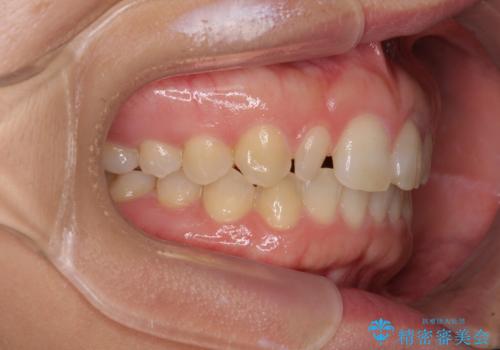

前歯の歯並びと小さい歯を改善 インビザラインとオールセラミッククラウン

- 前歯の空隙と矮小歯を気にして来院された患者様です。

上下の歯列不正はインビザラインにより整えることとしました。

矯正治療の後に、前歯1歯と奥歯をオールセラミックにて治療することとしました。

矯正治療により矮小歯前後にスペースを作りながら歯列を整え、セラミッククラウン装着後に最終的に歯列と咬合を仕上げました。